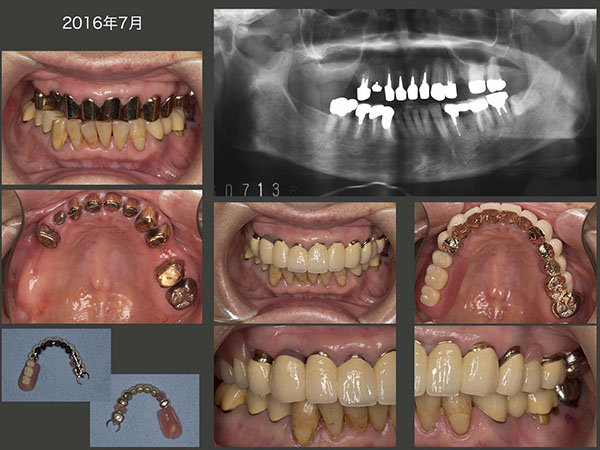

2016年7月,上顎一体型のコーヌス義歯が完成した.固定効果は十分に得られるが,右上4および左上4は無髄歯であることから,将来の歯根破折が心配であることに変わりはない.一方,左下6の根尖病巣はまだそのままであり,左下7の遠心の歯周ポケットも深い.本来は左下の治療も必要であるが,痛みがまだないので本人の治療承諾が得られていない.

1995年10月初診.49歳女性.主訴は歯周病の予防をしたい.歯周病の治療終了後に前歯の審美性向上を期待し,歯科矯正を行った.(スライド上段中央の写真は下顎前方位の状態)96年5月,治療は一段落ついた.その後定期的にリコールに応じてもらった.スライド中・下段に95年初診時から2009年までのパノラマX線写真を示す.歯のプラークコントロールは申し分ないが,咬合力が著しく強い.それが一番の原因と思われるが,咬合支持歯で主にここで食事をしていると思われる左上7を98年8月,左上4を00年6月,右上6を06年2月にそれぞれ歯周病で失った.なお,04年5月に右下5を歯冠破折から抜髄した.下顎2〜2の前歯は,咬合力によるアブフラクションおよび歯間ブラシの過度の使用から歯がすり減ったことが原因で抜髄した.

2012年9月,片側処理のコーヌス義歯を左右に装着した.いきなり両側性設計の義歯を装着すると違和感が生じやすいので,まずは口蓋を覆わない形にしたが,11月,装着して直ぐに右上4の歯周ポケットが悪化した.そこで直ぐに固定効果を増すために左右義歯床を連結する必要に迫られた.口蓋を覆う位置を実験的に検討したが,最終的に口蓋隆起を除去し,その空いたスペースに大連結装置を付与させてもらうということで了解してもらった.13年8月,パラタルプレートを装着し,両側性設計の義歯に改変した.